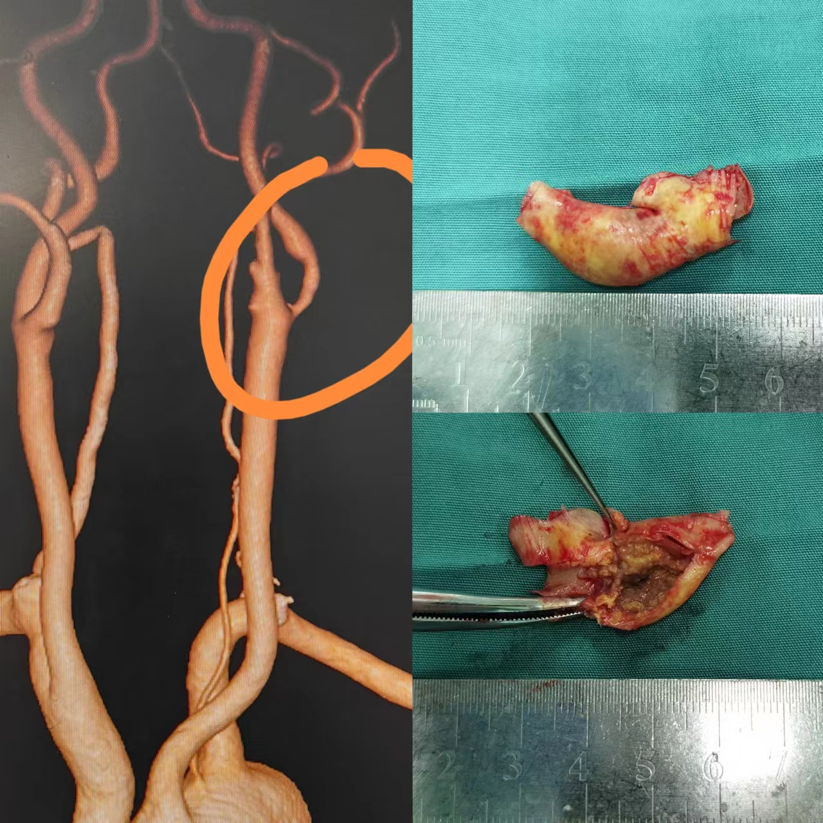

患者基本信息

基本信息:男性,58岁。

手术时间:2023年12月9日,术后第五天准备拆线出院。

术后恢复:活动自如,但在如厕时突发头痛、呕吐,随后发生脑出血,进行了血肿清除术。

术后医嘱:

阿托伐他汀钙片:20mg QN

利伐沙班:10mg QD

拜阿司匹林:100mg QD

氯吡格雷:75mg QD